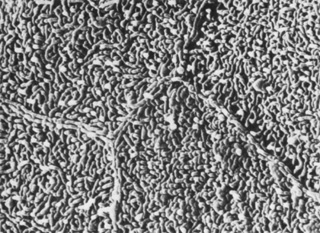

STROMA

The bulk of the cornea consists almost entirely of the corneal stroma, a fibrous tissue layer approximately 450 μm thick in the central cornea (Fig. 14). As determined by biochemical and immunohistologic methods, the stroma is composed predominantly of type I collagen with types III, V, and VI also in evidence.34,37,48 Immunogold labeling was intense for collagen type VI, which is associated with the interfibrillar matrix only and not localized to the striated fibrils.48 Type III and V collagens are codistributed with striated type I collagen. This codistribution is similar to the codistribution of types III and V in Bowman's layer. Type V and III collagens also have been labeled at the interfacial matrix separating stroma and Descemet's membrane.34,48

Fig. 14. Stromal collagen fibrils (c) in uniform spatial arrangement within orthogonal lamellae. A portion of a keratocyte is seen within the interlamellar space. Granular material (asterisk) is visible adjacent to the cell body (30,000×). (Courtesy of Drs. Rodrigues, Waring, Hackett, and Donohoo.)

Type I collagen is organized into striated fibrils 25 to 35 nm in diameter with periodic banding according to electron microscopy.46 Type V collagen appears colocalized with type I in the striated fibers.54 Using atomic force microscopy, corneal collagen was reported to have a D-periodicity of 63.9 to 68.5 nm.55,56 Scleral periodicity banding occurs at 67-nm intervals. Fibrils are composed of 4-nm microfibril components arranged in a right-hand helix and tilted at 15 degrees to the fibril axis in the cornea and 5 degrees in the scleral. This striated banding is the result of the offset, stacked arrangement of individual procollagen triple-helix molecules into units of five (the microfibril), which are further combined to form the basic unit of the collagen fibril. The 67-nm axial repeat was shown to correspond to the N– and C- telopeptids and the D-band periodic gap zone.57

These fibrils are combined into highly ordered, sheet-like bundles called lamellae, which lie essentially parallel to the corneal surfaces. Lamellae vary in width and thickness throughout the stroma, with a tendency to have smaller dimensions anteriorly (0.5 to 30 μm wide and 0.2 to 1.2 μm thick) and larger dimensions posteriorly (100 to 200 μm wide and 1 to 2.5 μm thick).46 Hundreds of individual lamellae can be discerned in a cross-sectional slice of the full-thickness central cornea.